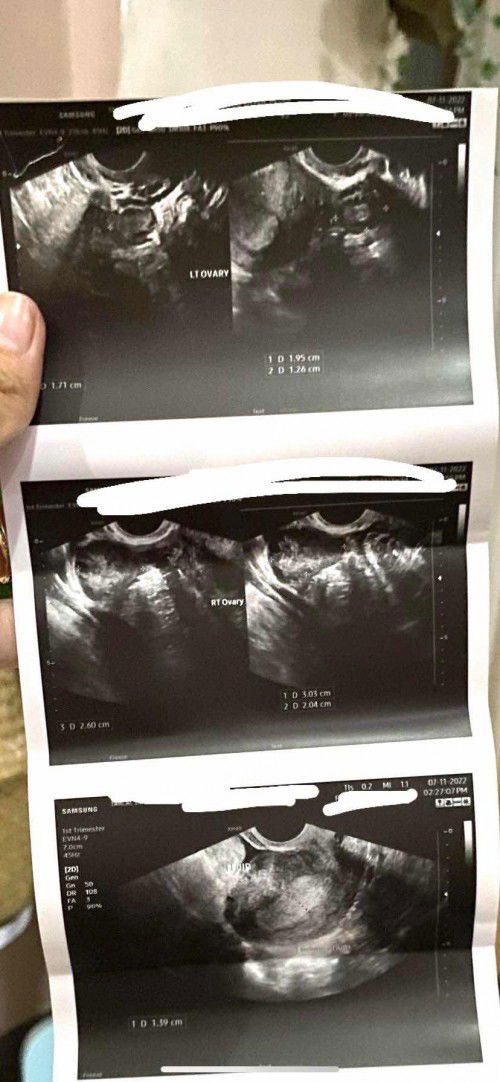

Hello po last menstruation ko noong May 22. Nag-pt po ako positive naman, ask ko lang po kasi nagpatransv ako last week, wala pa nakikita sa uterus ko. Normal lang po ba yun? Sabi ng doctor ko either early pregnancy or ectopic huhu pls help π₯ im worried po thanks sa answer niyo mommies! #pregnancy #firstbaby #pleasehelp